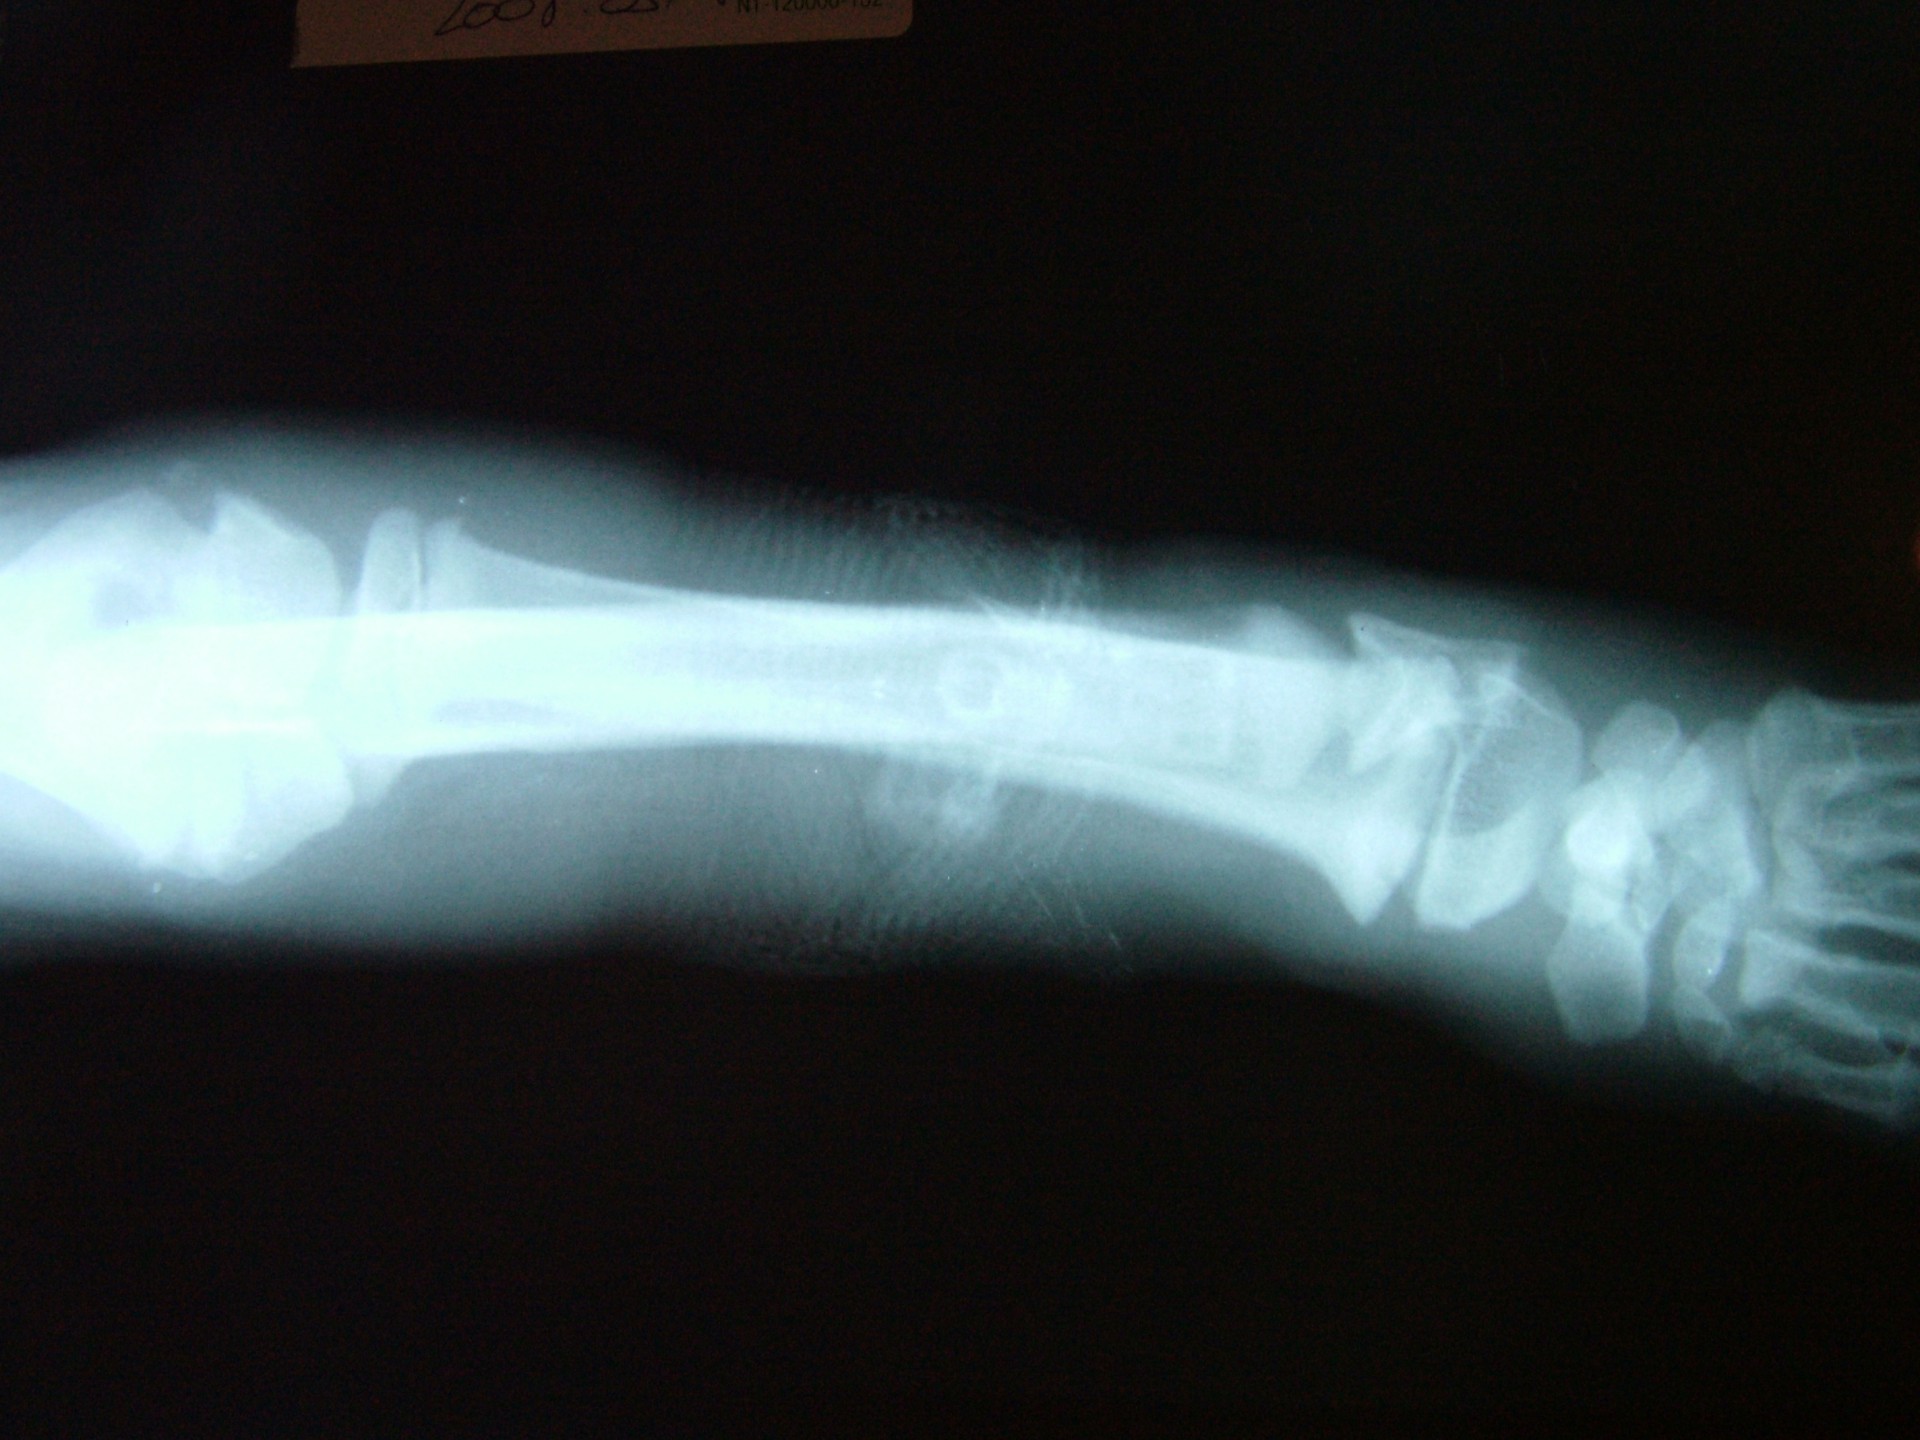

A betegségre jellemző, hogy az ébren klinikai tüneteket mutató állatok altatásban történő vizsgálata (az izmok ellazulása miatt)valamint az érintett végtagról készült röntgen vizsgálat mindig negatív eredménnyel zárul, a csontozatban rendellenesség nem mutatható ki.

A diagnózis felállítása során a legfontosabb, hogy kizárjuk a szintén fiatal állatokra jellemző, a csövescsontok növekedési zónájának lezáródásából adódó végtagdeformitást.